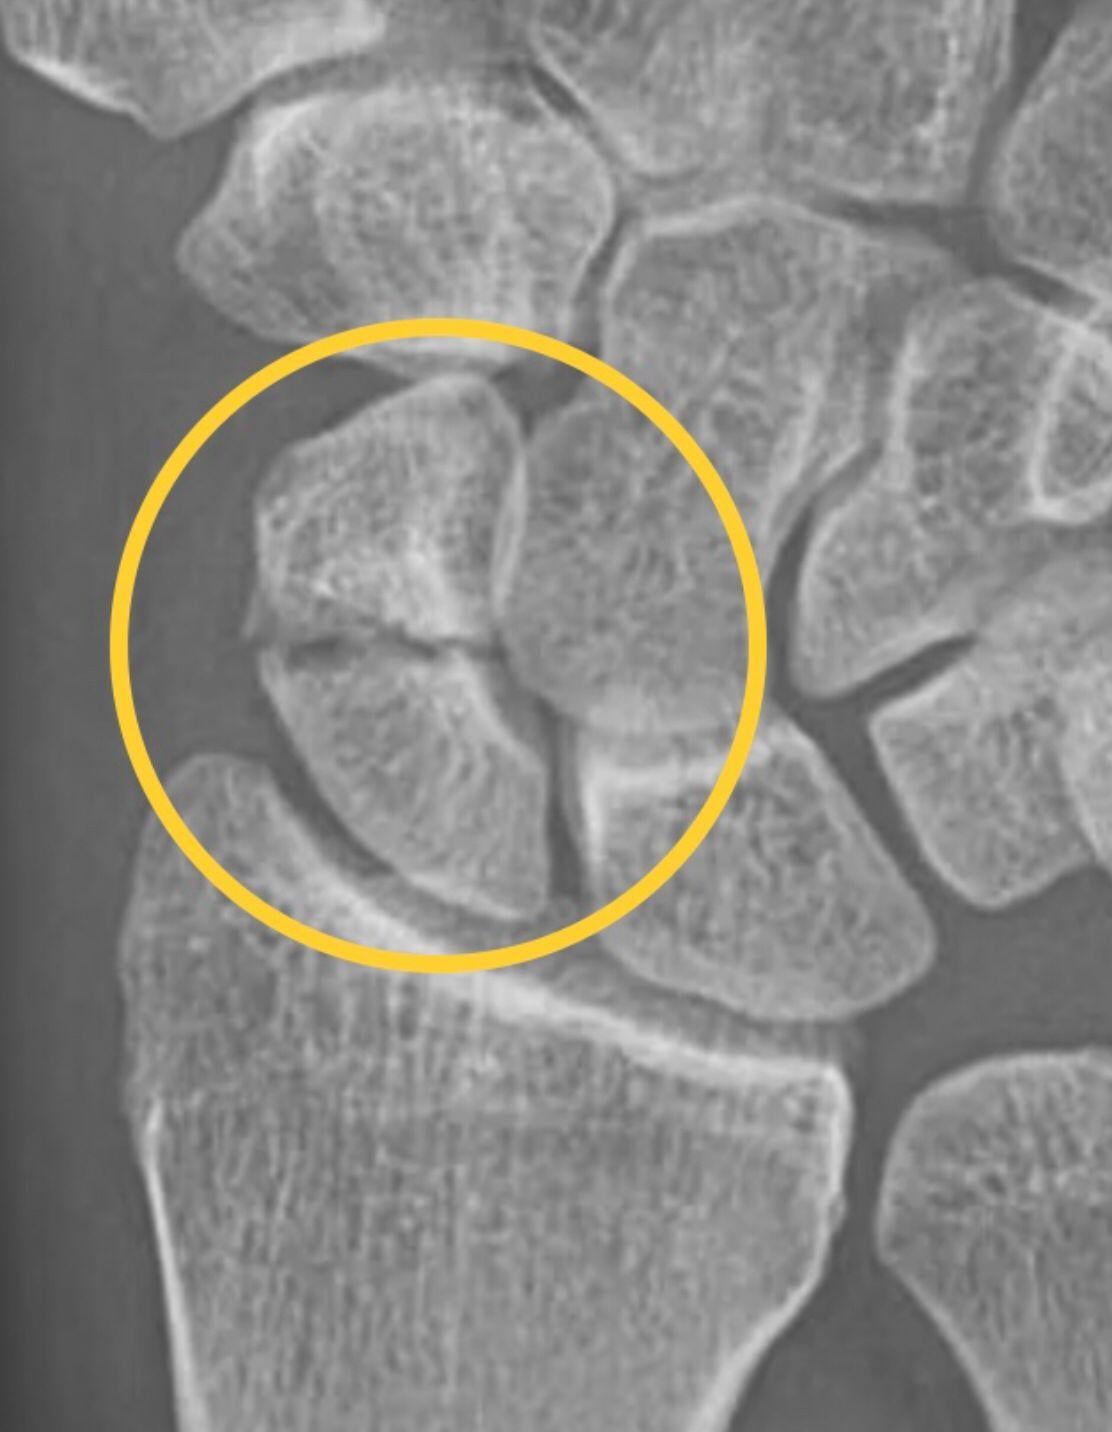

我們的手腕有八塊腕骨,當中因形狀似船而得名的舟骨,是最容易出現骨折的腕骨。舟骨位於拇指底部與手腕橈骨之間,當意外跌倒時用手撐地,除了可導致遠端橈骨骨折外,亦可造成舟骨骨折。骨折後,因不少病人只感到腕部隱隱作痛,往往延誤了求醫;但另一方面,有近三成骨折在早期X光下卻不甚明顯。故此就疑似個案,須及早照電腦掃描或磁力共振來斷症,且暫時當骨折處理,先以石膏來固定手腕,以防隱性骨折在毫無保護下出現移位。

然而舟骨的獨特之處,在於它主要的血液供應,來自逆行的橈動脈分支,猶如「逆水行舟」從舟骨遠端流向近端。舟骨骨折較多發生於舟骨中段,但倘若骨折位置愈靠近近端,便愈容易因供血中斷而併發成骨折不愈合、缺血性壞死,甚至出現恍如沉船的晚期塌陷。此外,因舟骨與附近腕骨互相連繫,對日常手腕活動尤其重要。倘若骨折在移位下愈合,或是因缺血而壞死,也會像「火燒連環船」般牽連毗鄰腕骨,造成腕關節退化,帶來疼痛和僵硬等問題。